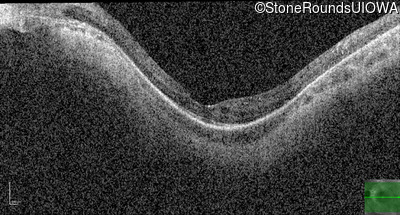

Optical Coherence Tomography - Left - 20/32 +2

Exemplar / OCT Stack

OCT Stack